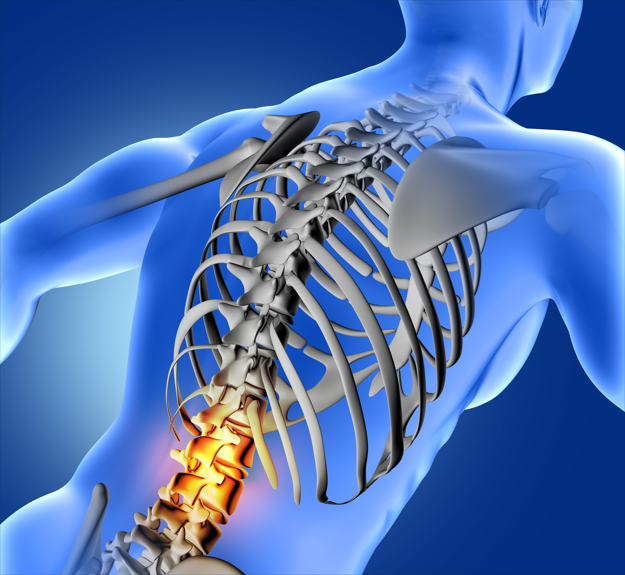

목 · 허리통증

[ Neck and Back Pain ]

허리 통증은 평생을 살면서 70~90%의 사람이 경험하는 것으로 알려져 있습니다.

처음에는 가벼운 통증으로 시작하지만, 점점 부위가 넓어지고 닳게 되면서 퇴행성 변화를 일으키게 됩니다.

척추와 그 주변 구조물들은 한번 손상되면 재생이 잘 되지 않고, 노화에 따라 더 자주 발생하기도 합니다.

무엇보다 적절한 시기에 개인에 맞는 진단 및 치료가 필요하며, 평상시에는 나쁜 자세나 습관을 고치는 것이 급선무입니다.